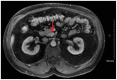

Pancreaticoduodenal artery aneurysms (PDAAs) are an extremely rare visceral artery aneurysm subtype, usually managed by endovascular techniques. We report the case of a 57-year-old man with an intrapancreatic, inferior PDAA abutting the superior mesenteric artery (SMA). This location, in relation to the SMA, risks SMA thrombosis using an endovascular-only approach. Our approach consisted of open exploration and ligation of the inferior PDAA junction at the SMA, followed by endovascular coil embolization of the aneurysm. This case serves as a reminder that although many vascular diseases can be treated with less invasive endovascular strategies, open surgery can sometimes be the safer alternative.